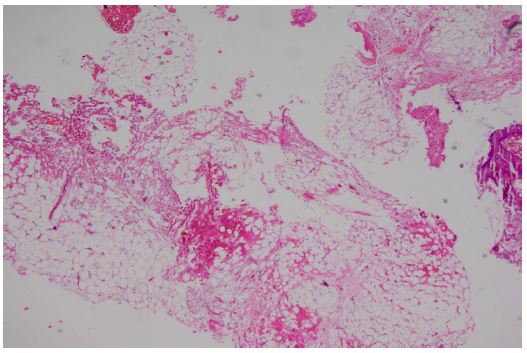

Figure 4: The biopathology examination showed the fibrous fat and a small amount of mucosal tissue. HE 40×.

Figure 5: The biopathology examination showed the fibrous fat and a small amount of mucosal tissue. HE 100×.

The biopathology examination showed the fibrous fat and a small amount of mucosal tissue (Figure 4-5).